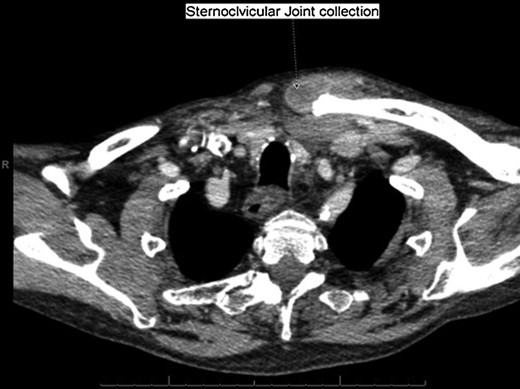

With a working differential of parapharyngeal space infection and possible malignancy, the patient was referred for a computed tomography (CT) scan of the neck and thorax with contrast. The patient was also started empirically on intravenous co-amoxiclav as treatment for neck space collection. CT imaging, performed 24 h after admission, revealed no evidence of malignancy or indeed any paraphayrngeal space collection. Few small lymph nodes were noted on the left side of the neck, but were deemed to be reactive in nature, and left vocal cord palsy was evident (Fig. 1). The key finding was that of a left sternoclavicular joint collection and closely associated superficial anterior chest wall, soft tissue swelling and oedema (Fig. 2). This inflammatory process was also noted deep to the manubrium and sternum and extending somewhat into the mediastinum with evident enlarged mediastinal lymph nodes (Fig. 3). The CT findings were in keeping with SSA with associated superficial and deep tissue inflammation and oedema. With no other cause found, the vocal cord palsy was attributed to the inflammation within the mediastinum, which in turn was caused by superficial burn from hot water bottle use.

Computed tomography. A 67-year-old male with SSA. Findings: left sternoclavicular joint collection and closely associated superficial anterior chest wall, soft tissue swelling and oedema. The oedema can be seen to be spreading into the chest. Technique: contrast-enhanced axial CT of the neck and thorax.